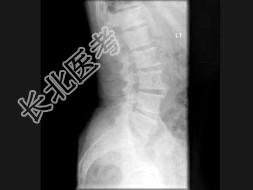

- 单项选择题男,77岁, 全身性骨痛,夜间加重, 贫血,PSA大于100, 结合图像,最可能的诊断是 ( )

A、成骨性骨转移

B、多发性骨髓瘤

C、慢性化脓性骨髓炎

D、骨肉瘤

E、以上都不是